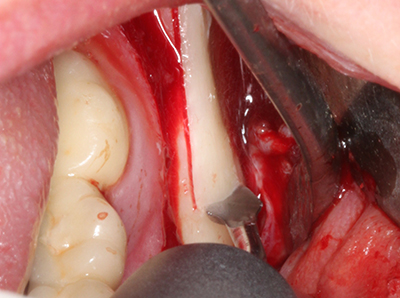

Bei der Knochenblockentnahme zeigen sich weitere Vorteile für die Piezochirurgie: Neben der bereits beschriebenen hohen Präzision bei der Osteotomie stellt sich gerade die Verwendung der dünnen Sägespitzen als besonders materialschonend heraus. Bei der Verwendung insbesondere von Lindemannfräsen sind mit deutlich höheren Entnahmeverlusten durch die dickere Instrumentenspitze zu rechnen (Lakshmiganthan, Gokulanathan et al. 2012). Die insbesondere bei retromolar entnommenen Blocktransplantaten notwendige basale Abtrennung wird durch speziell hierfür vorgesehene rechtwinklige Sägen erleichtert, so dass die Piezochirurgie als präzises, übersichtliches und sicheres Verfahren zur retromolaren Knochenblockgewinnung angesehen wird (Happe 2007) (Abb. 1-12).

Sollen chirurgische Eingriffe mit unmittelbarer Knochenbeziehung an empfindlichen Strukturen wie Blutgefäßen oder Nerven erfolgen, so bergen rotierende Instrumente ein erhebliches Potential an iatrogener Schädigung. Gerade bei Nervdarstellungen nach iatrogener Schädigung, oder aber im Zuge einer Nervlateralisation für resektive und rekonstruktive Eingriffe oder Implantatinsertionen können piezoelektronische Geräte hilfreich sein Knochendeckel zu präparieren und nervnahe Hartgewebsanteile zu entfernen (Abb. 17-20). Ein leichter Kontakt des Nervstrangs zur Piezospitze bleibt dabei in der Regel folgenlos – allerdings kann eine unvorsichtige Vorgehensweise mit sägeartigen Bewegungen bzw. Ansätzen bei noch vorhandener knöcherner Unterlage durchaus temporäre oder aber auch permanente Nervschädigungen verursachen. Das Risiko einer solchen Schädigung wird jedoch als wesentliche geringer eingeschätzt als unter Anwendung von Säge- oder Fräsinstrumenten (Pereira, Gealh et al. 2014).